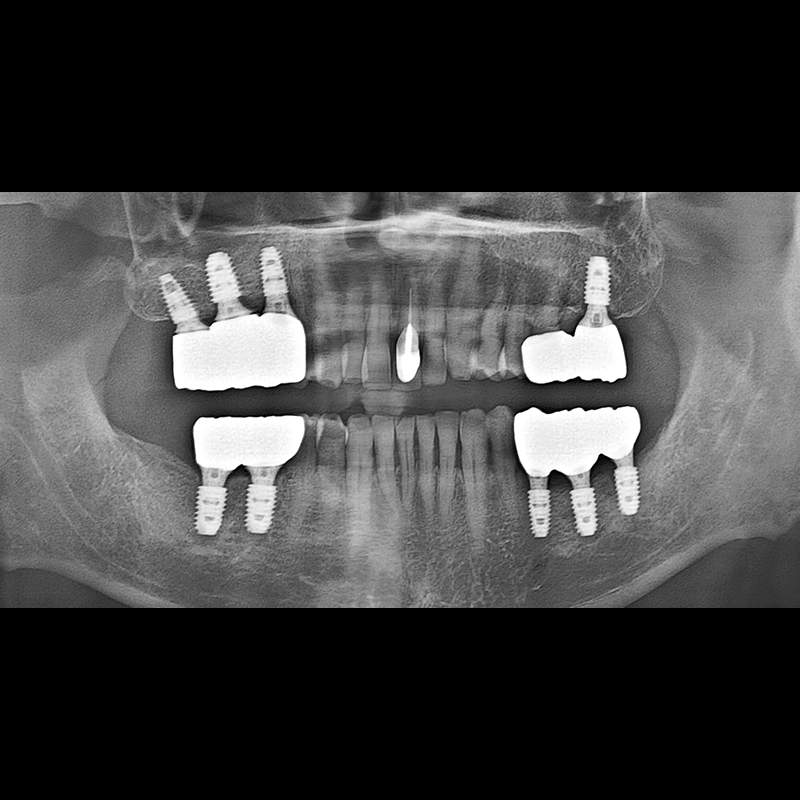

BEFORE AFTER

种植牙前后的照片 2025.05.30

在缺失的牙齿部分和难以挽救的牙齿位置植入了种植牙。